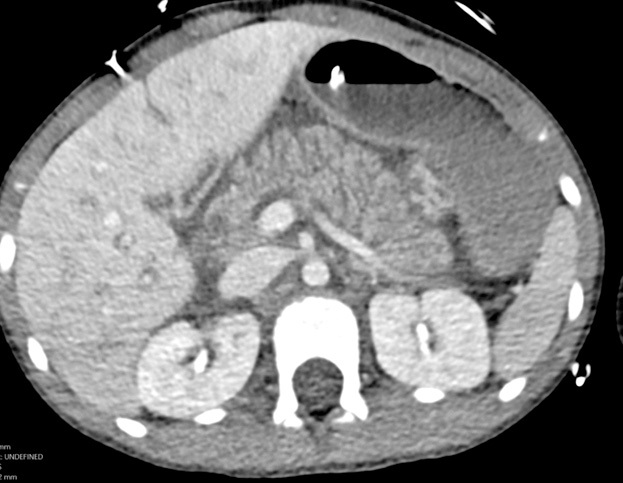

Abdominal injuries due to bicycle handlebars are of particular importance in children. Half of children with a handlebar injury have serious abdominal pathology. The most common organs involved include the pancreas, spleen, liver, small bowel, and mesentery. Handlebar injuries are the most common cause of pancreatic trauma in children. Children who have experienced a handlebar injury should undergo an abdominal CT with intravenous (IV) contrast, since these injuries are unlikely to be diagnosed using abdominal X-rays or FAST exam.53 See Figures 6 and 7 for an example of a pancreatic injury. Figure 8 depicts a small bowel injury.

Figure 6. Enlarged, Edematous Pancreas |

Enlarged and edematous pancreas without a focal laceration or defect, consistent with traumatic pancreatitis Source: Courtesy of Sean Kelleher, MD, Dayton Children’s Hospital, Department of Radiology |

Figure 7. Transection of Pancreas |

Axial and coronal images from computed tomography with intravenous contrast show a complete transection through the body of the pancreas. Source: Courtesy of Mark Warren, DO, Dayton Children’s Hospital, Department of Radiology |